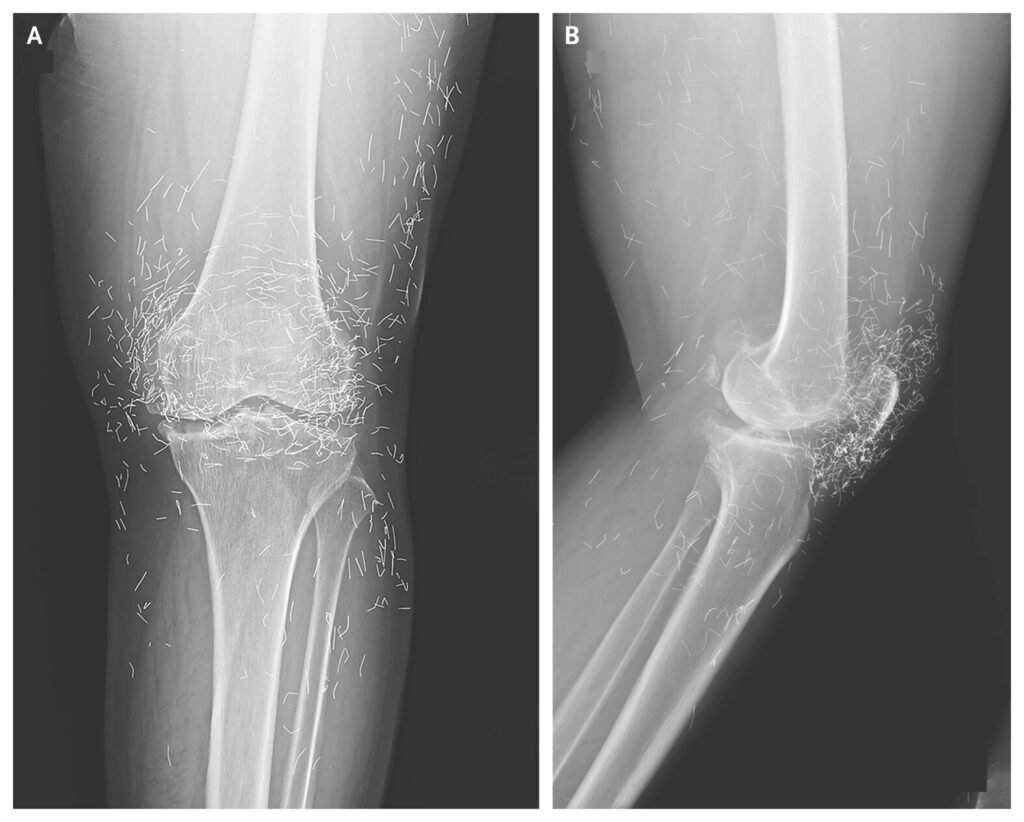

É um corpo estranho dentro do organismo. Isso infelizmente não tem como ser removido. Como é um corpo estranho, pode gerar um quadro de infecção. A paciente foi atrás de um tratamento alternativo para uma doença que tem tratamento eficaz e arrumou um problema que vai acompanhá-la para o resto da vida.

— Alexandre Pena, ortopedista da Beneficência Portuguesa